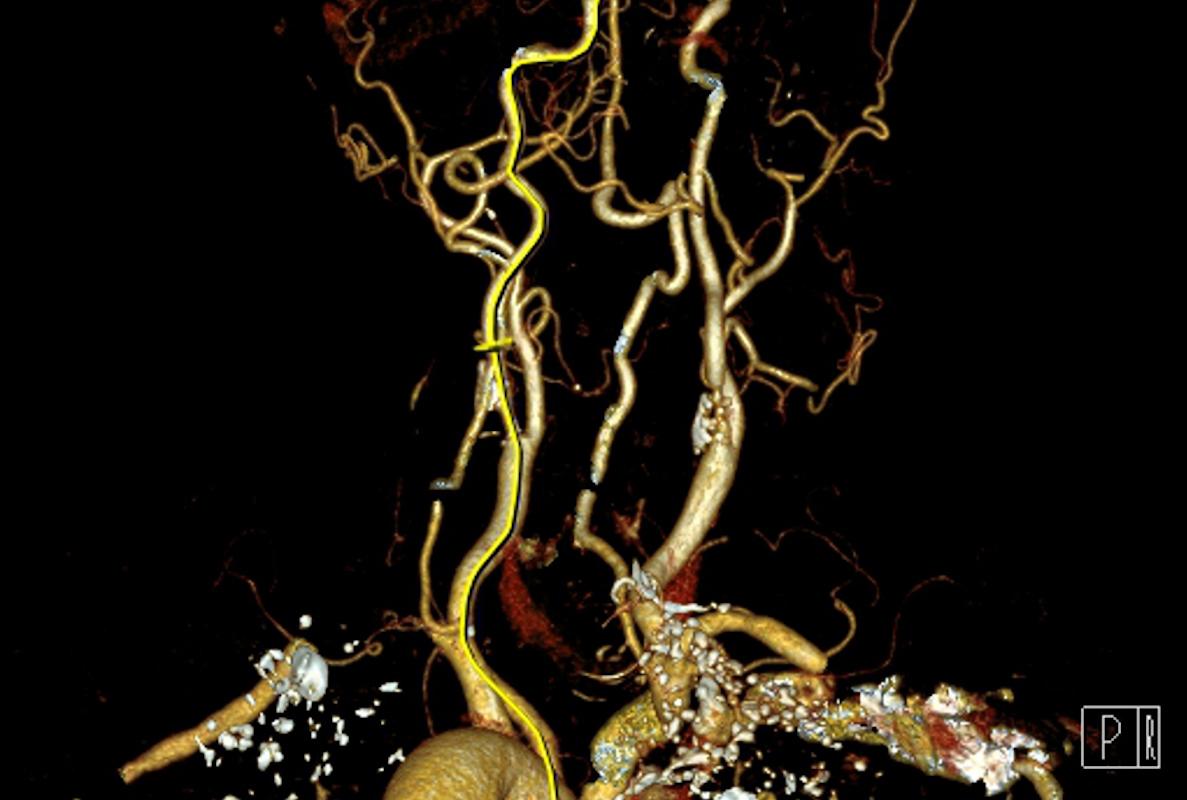

Le journal The Telegraph se fait l’écho d’un cas clinique extrêmement rare, et tout autant fascinant – d’un point de vue médical. Après s’être assurés que la masse constatée n’était pas liée à un cancer, les chirurgiens de l’hôpital de Chypre décident d’opérer cette mère de famille londonienne de 45 ans, expatriée sur l’île. Ils craignent alors que le kyste ne se détache, mettant en danger la vie de la patiente.

L’opération dure trois heures, au terme de laquelle ils extraient, avec stupeur, non pas un kyste, mais un fœtus « fossilisé », doté d’un visage, d’un œil, d’une dent et d’une longue chevelure brune, semblable à celle de Jenny Kavanagh. En fait, il s’agit là de son jumeau, qui, pendant 45 ans, s’est développé à l’intérieur d’elle.

De fait, au cours de la gestation de jumeaux, il arrive que l’un des deux fœtus migre à l’intérieur de l’autre. Cette anomalie, appelée « fœtus in fetu », a été décrite pour la première fois par l’anatomiste allemand Johann Friedrich Meckel à la fin du 18e siècle. Depuis, une centaine de cas ont été rapportés dans la littérature. En général, les deux fœtus meurent avant la naissance, mais, si ce n'est pas le cas, il arrive que le fœtus « parasite » reste à l’intérieur de son hôte pendant des années.

Le fœtus in fetu, lui, présente déjà une organisation telle que l’on peut y observer des vertèbres, des membres ou encore des tissus organiques (dents, ongles, cheveux...). Il se nourrit de son environnement (en l’occurrence, un ovaire), mais, bien sûr, il n’a ni cœur battant, ni sang circulant.